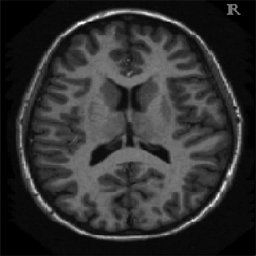

4.1. Uniform Gaussian noise

In this first experiment, we consider the denoising problem with brain scan images. The first set consists of images of pixels and Gaussian noise with zero mean and variance . The original and noisy images are shown in Figure 4.1. The domain decomposition-semismooth Newton algorithms run with the parameter values , , and . The results are shown in Figure 4.2. From the surface representation of , we can observe that is continuous and its shape is related to the one of the original image. In particular, the regularization is stronger in homogeneous regions in the image, and weaker where the image intensity undergoes variations on a smaller scale.